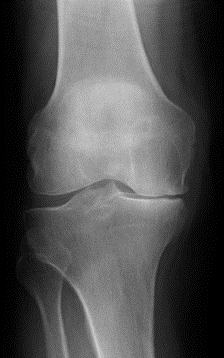

Ms Chloe Scott is a Consultant Trauma and Orthopaedic Surgeon with a specialist interest in hip and knee arthroplasty and lower limb trauma. She has a particular expertise in partial knee replacement surgery, robotic assisted joint replacements and in complex knee replacement surgery including revision.

Ms Scott graduated from the University of Edinburgh medical school in 2004. She completed her orthopaedic training in Edinburgh during which time she also completed higher degrees in Orthopaedic Engineering at Cardiff University and in partial knee replacement design at the University of Edinburgh. She completed travelling fellowships in Boston, Chicago, and South Carolina USA.